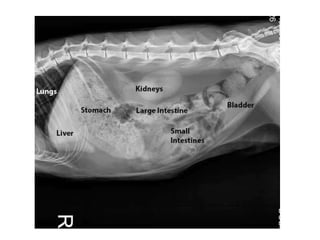

Left lateral image